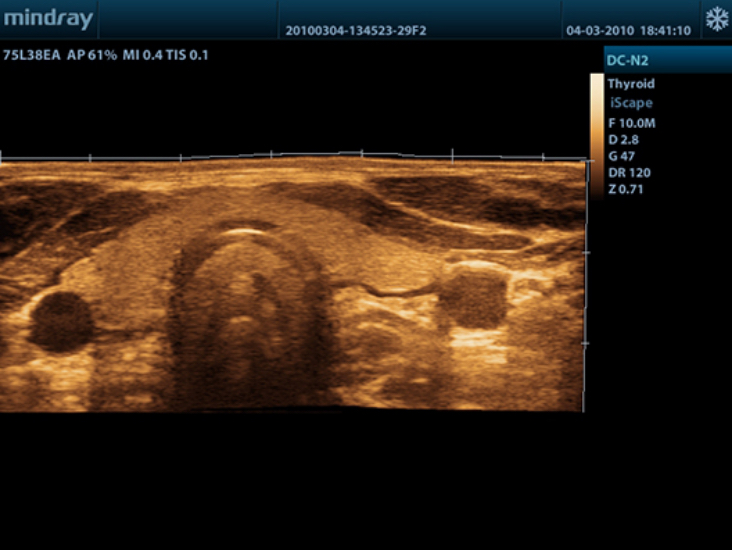

DC-N2

Color Doppler within Reach

DC-N2 offers a unique combination of relevant technology, quality and affordability. Be it an experienced ultrasound professional or a beginner, the DC-N2, with its unique self-learning software and advanced imaging technologies can be used across multiple clinical settings. With a user-friendly control panel and a user-centric workflow system, the DC-N2 can be well trusted for its performance and ease of use.

ExFOV

Discover better diagnostic information through extended view of the anatomical structure on all convex and linear probes.